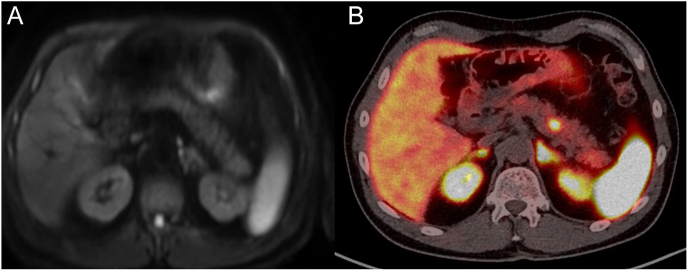

Results: In total, 85% (n = 39/46) of patients with MEN-1 had a 68Ga-DOTA-TATE PET/CT study in the electronic patient record; 23 of those with duodeno-pancreatic lesions detected also had contemporaneous contrast-enhanced CT scans, while 18 had MRI scans. 68Ga-DOTA-TATE PET/CT detected a total of 47 pancreatic lesions compared to 25 on CT, while 68Ga-DOTA-TATE PET/CT detected 32 pancreatic lesions compared to 25 on MRI. There were no duodenal lesions detected on conventional CT or MRI, but in comparison to CT and MRI, 68Ga-DOTA-TATE PET/CT detected eight and one duodenal lesions respectively. While 68Ga-DOTA-TATE PET/CT detected more liver metastases compared to CT (n: 31 vs 21) and similar numbers compared to MRI (n: 11 vs 11), these differences were not statistically significant. As a result of findings on 68Ga-DOTA-TATE PET/CT, a change of management was indicated in 69% (n = 27/39) of patients. Of these, 14 patients were offered somatostatin analogues (SSTA), eight patients were offered surgical intervention, three patients were offered peptide receptor radionuclide therapy, and one patient was offered ablation of liver metastases.

Conclusions: In patients with MEN-1, 68Ga-DOTA-TATE PET/CT was shown to detect a greater number of duodeno-pancreatic lesions compared to conventional cross-sectional CT or MRI imaging. Management plans were changed in most patients following their initial 68Ga-DOTA-TATE PET/CT. Therefore, we suggest that somatostatin receptor-targeted PET/CT scans should be an integral part of the investigation of patients with MEN-1 for staging of suspected duodeno-pancreatic NETs.